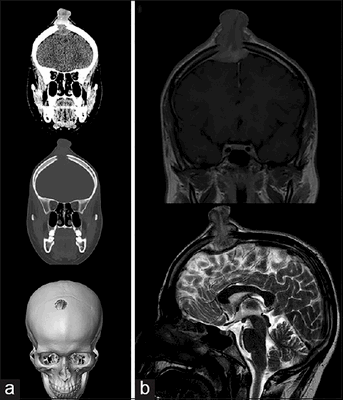

Молодой человек 17 лет был госпитализирован по поводу увеличивающегося в течение последних 6 недель образования волосистой части головы. Образование при пальпации болезненно, из‑за изъязвления периодически кровоточит, однако неврологического дефицита не выявлено. При КТ и МРТ выявлен крупный очаг в лобной кости справа, сдавливающий верхний сагиттальный синус. Проведена тотальная резекция образования, подтвержден диагноз «лангергансоклеточный гистиоцитоз кости черепа». На амбулаторном этапе проводилась терапия цитостатиком.

Рисунок 6. (а) КТ-исследование без контрастирования — фронтальное сканирование (верхняя и средняя часть) и 3D-реконструкция черепа (нижняя часть). (b) МРТ-сканирование. Т1‑взвешенное изображение во фронтальной плоскости (сверху) и Т2‑взвешенное изображение в сагиттальной плоскости